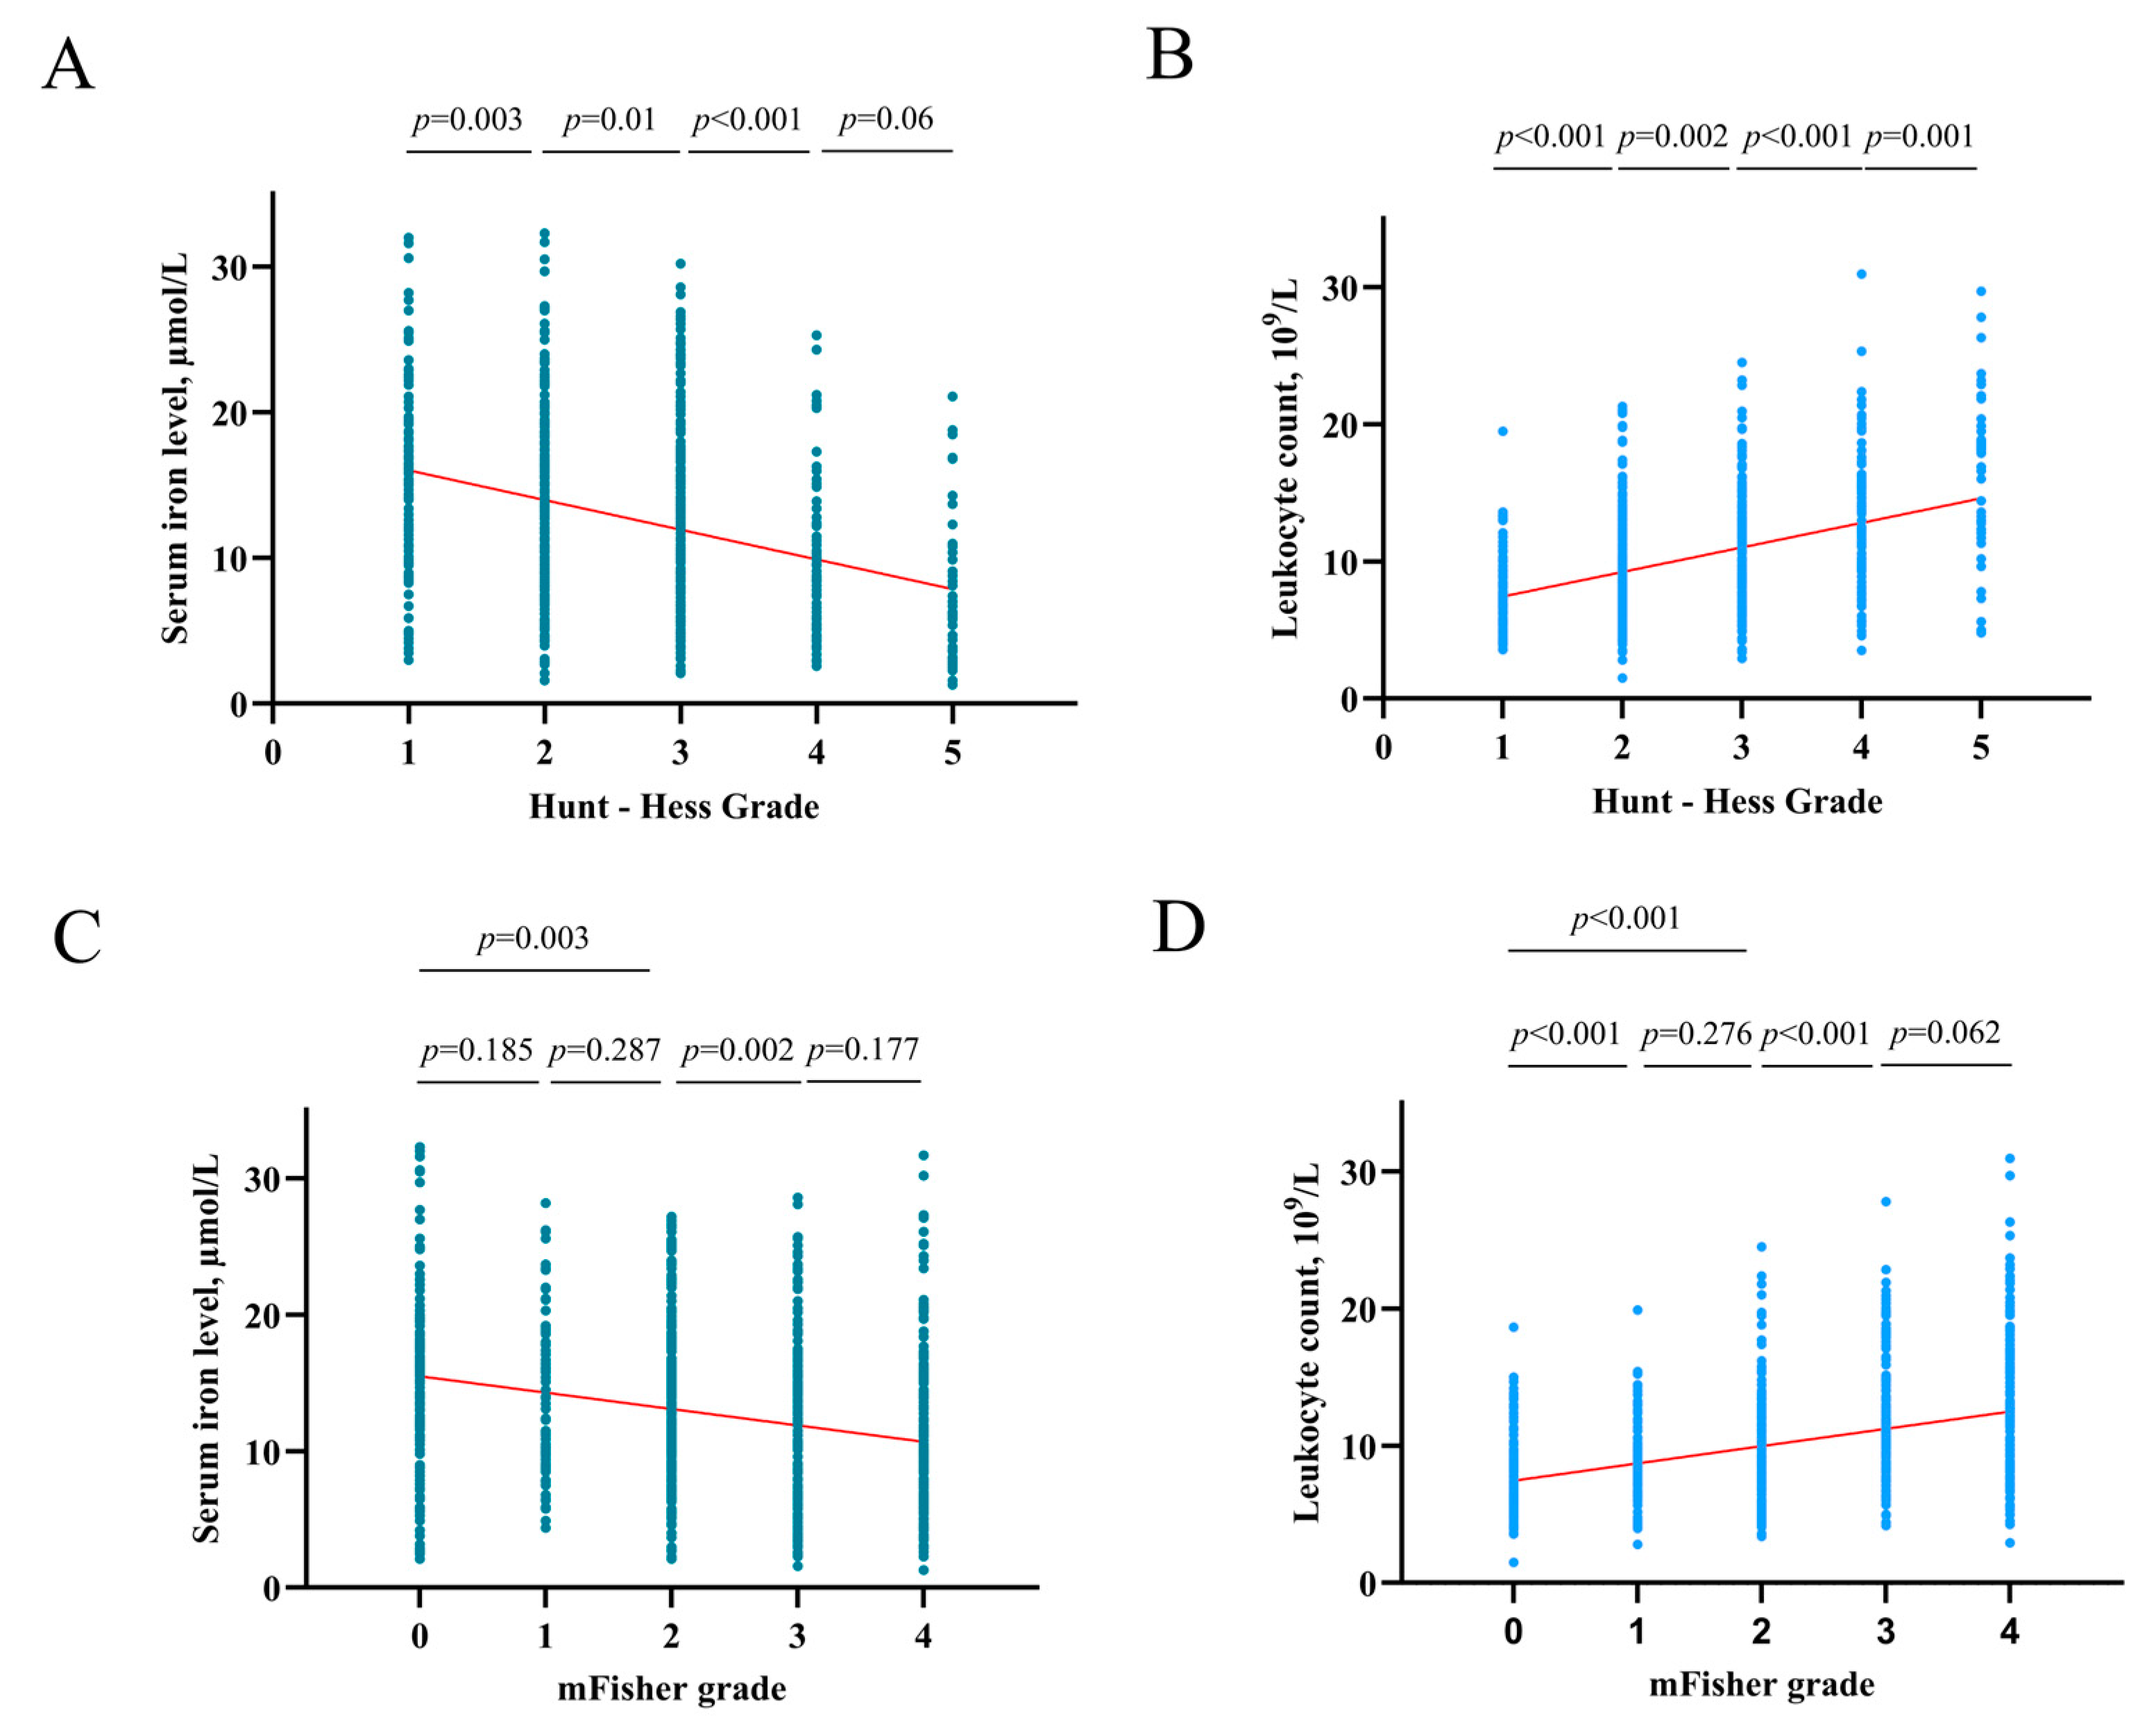

4.3. Association of Serum Iron with HHgrade and mFisher Grade

4.4. Association of Serum Iron with Poor 3-Month Functional Outcome